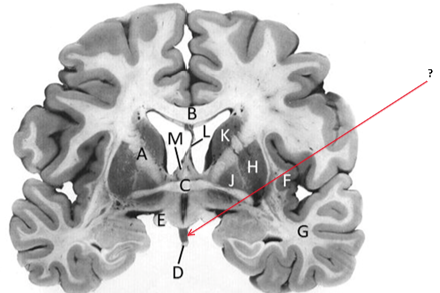

Name this and state its function.

Corpus Callosum.

Putamen.

Name this, state its function, pathways and cellular components.[5 marks]

Caudate nucleus.

Medium spiny neurons utilising GABA and some Cholinergic.

From cortex–>CN–>hippocampus, Gp and thalamus.

Septum pellucidum.

Fornix.

Anterior commissure.

Interconnects:

Infundibular stalk.

Insula.

Name this, state its function, components[2] and the difference in pathways.

Internal capsule.

Anterior limb:

Posterior limb:

Corticospinal tracts and corticopontine tracts: